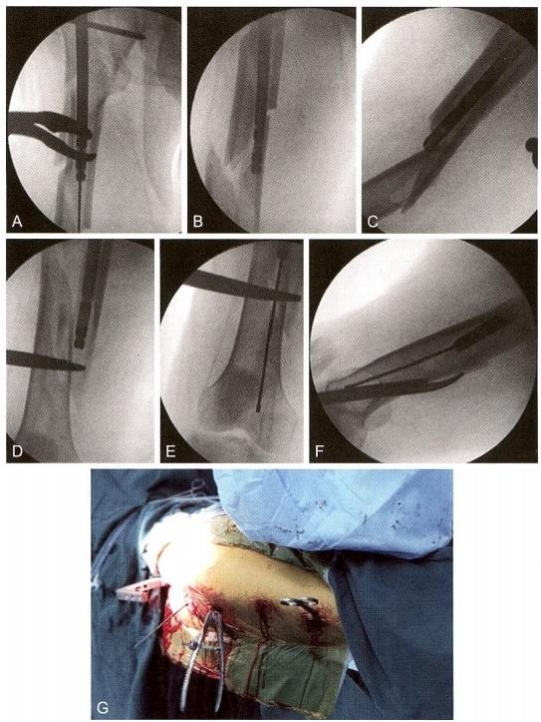

(1)**步:复位。

透视下见髋内翻,外侧皮质张口,侧位见转子下骨折块前后劈裂移位,外侧经皮钳夹复位转子下骨折块(图12-10)。

图12-10 复位。A.经皮纠正髋内翻;B.侧位见骨块前后移位;C. 经皮钳夹复位后正 位;D.经皮钳夹复位后侧位

(2)第二步:开口。

经大转子向股骨颈方向钻入一枚直径3.5 mm 的克氏针开展joystick 技术,紧贴后方骨皮质,避免影响近端钉道,内收、内旋髋关节,有利 于暴露大转子顶点。经大转子顶点钻入导针,侧位导针方向略偏前,近 端扩髓后插入导针(图12-11)。

图12-11 撬拨。A.内收、内旋髋关节;B.插入导针,侧位显示导针位置良好;C. 正 侧位显示导针位置良好;D.导针通过粉碎骨折段

(3)第三步:扩髓插钉。

利用“复位手指”器或者直径最小的髓内钉来控制导针的插入,股骨 远断端由于重力和小腿三头肌的牵拉而向后移位,通过经皮撬拨抬高远 端,使导针紧贴前方皮质插入股骨髁(图12-12A-G)。 术中采用经皮钳 夹、经皮撬拨和joystick 技术。

图12-12 扩髓插钉。A. 插入髓内钉;B.用髓内钉进行撬拨复位;C.侧位显示远端骨 块向后成角移位;D. 撬拨复位+joystick 技术复位移位段;E. 插入导针达远端髓腔内, 正位;F.导针达远端髓腔,侧位;G.术中照片

(4)第四步:近远端锁定。近端经股骨颈锁钉固定后,远端徒手植 入3枚锁钉,多平面固定微创手术切口(图12- 13)。

图12-13 近远端锁定。A. 近端经导向架植入导针;B. 近端头颈部用2枚螺钉锁定;C. 远端用3枚螺钉锁定;D.远端侧位透视示螺钉位置正确;E. 术中照片显示微创闭合 复位